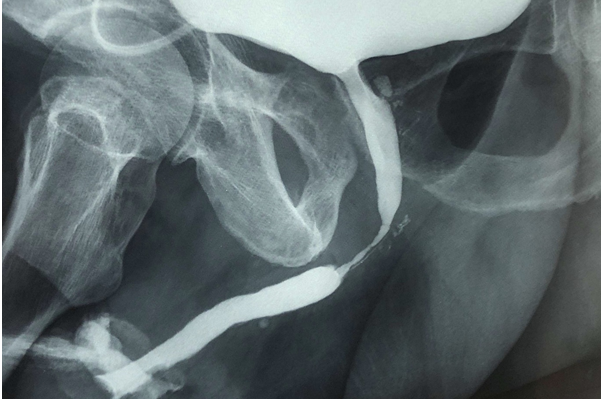

- d’une urétrocystographie rétrograde et per mictionnelle sous anesthésie locale et injection de produit de contraste, pour observer la totalité de l’urètre, localiser de manière précise le rétrécissement et estimer sa longueur et son degré de sévérité, observer l’état de la vessie et de l’urètre en avant de la sténose ;